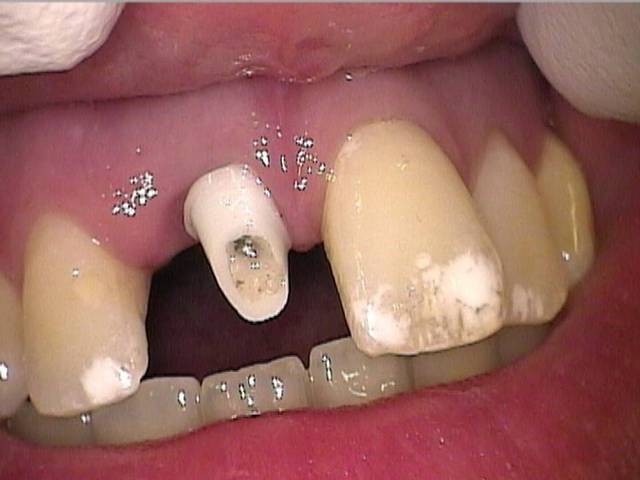

Photos d'un cas d'extraction implantation immédiate, stabilité primaire (de mémoire) assez élevée.. 60/70 N ..démontage du gingiva clips et du shuttle, pilier serré 40N, couronne procera

Merci pour le cas, bien fait. Belle présentation photo.

Le contour gingival est net, belle guérison, c'est à combien de semaine ?

Oui je sais pour le ciment... j'utilise d'ailleur ce cas et cette radio dans une présentation pour mettre en garde sur le risque au moment du scellement de voir du ciment fuser sous la limite prothétique vers la col de l'implant..galère à éliminer...Personnellement je préfere plutot utiliser des piliers à usiner (maintenant disponibles voir shop online pour photos) au lieu des strandarts meme si il y a deux hauteurs/col implantaire en 1 et 3mm aujourd,hui disponibles..A l'époque de ce cas il n'y avait que les 1 mm et la limite est un "poil" trop profonde.

La pose de la couron nec'est faite 8 semaines apres l'extraction implantation immédiate, la particularité de ce systeme permet de ne pas démonter le shuttle ni la gingivaclip pour l'empreinte..je pense que ca aide bien à la qualité gingivale...radio controle ci jointe